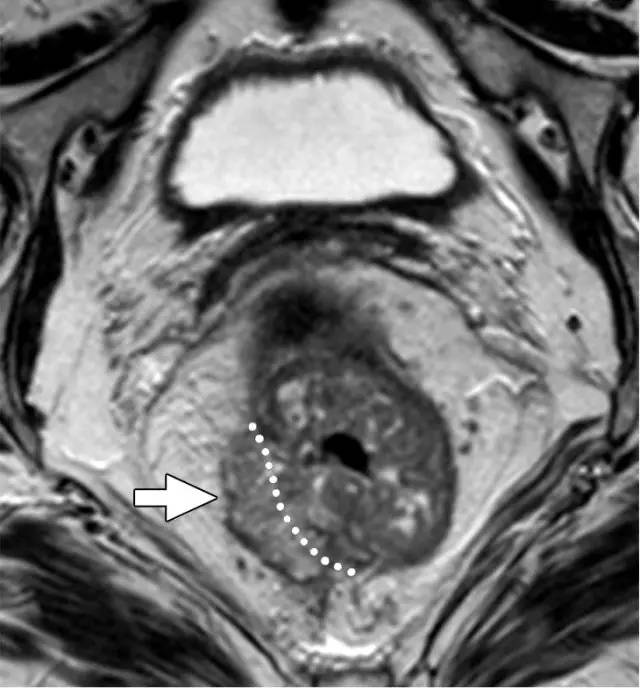

T3 分期

MRI 检测直肠周围组织浸润的敏感性为 82%,肿瘤侵犯或结缔组织增生反应均可表现为直肠周围浸润,为了避免分期不够,出现直肠周围浸润即作为 T3 期肿瘤。

图 6 T3 直肠癌 MRF-,肿瘤浸润直肠系膜,1~4 点钟位置